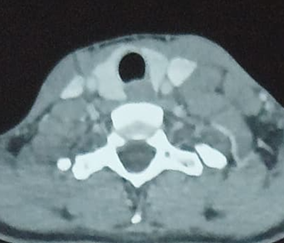

which remains permeable. The radiological exploration was complemented by a

computed tomography revealing multiple lymph node-like structures of the left

supraclavicular region measuring 2 cm × 3.8 cm in diameter (Figure 1).

Figure 1: Axial CT scan